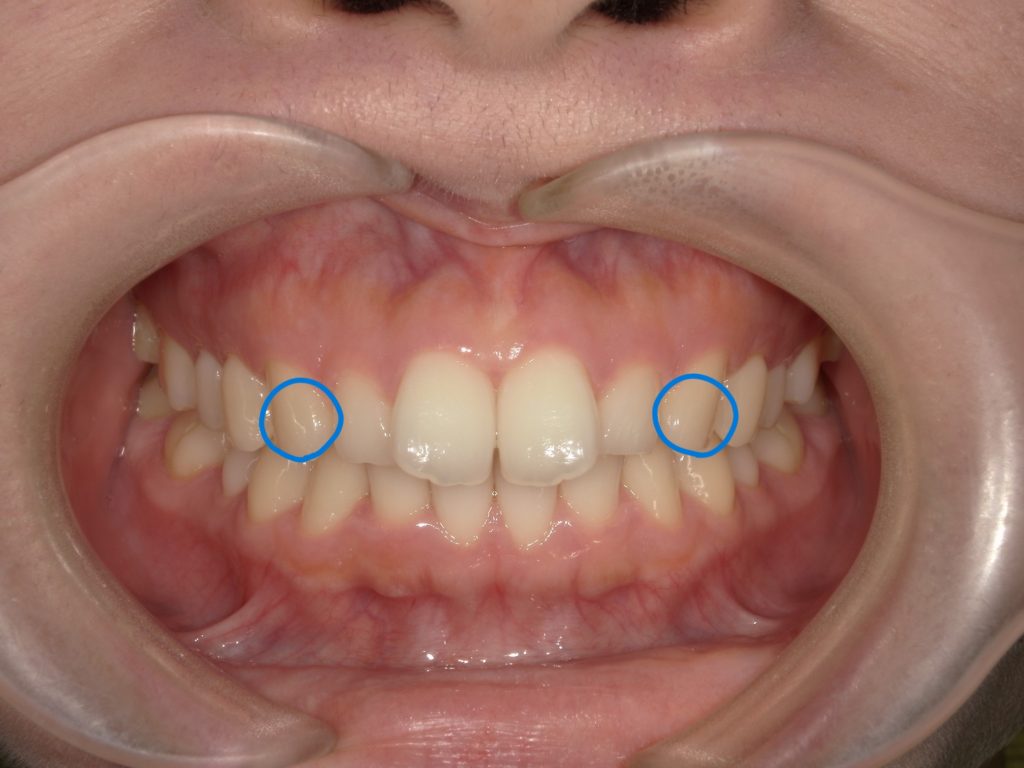

まず、部分矯正の方は前歯の3番目の歯から反対側の3番目まで装置を着けます💡↓ ↓

(青丸から青丸のところまで!)

今回は上の歯のみに装置を付けて治療を行いましたが、上下部分を希望される場合は下の歯も同様に3番目の歯から反対側3番目の歯に装置を付けます🦷